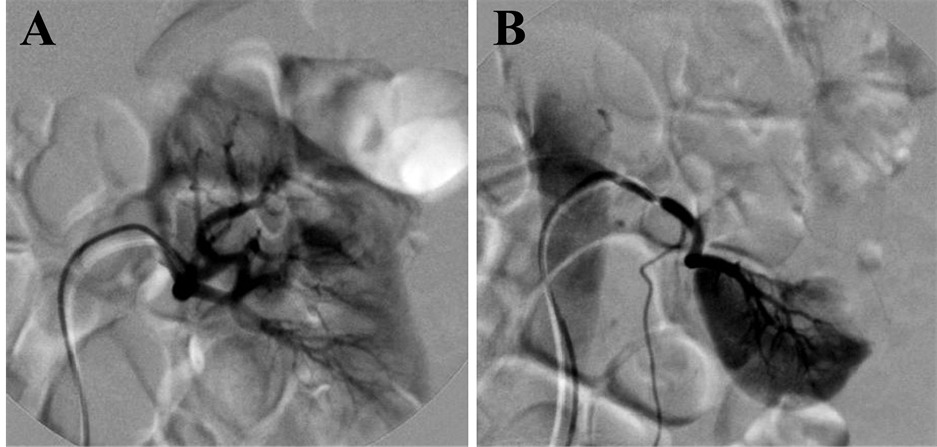

After informed consent was obtained from the patient and his immediate family members, digital subtraction angiography (DSA, OEC9800 C-arm X-ray system, GE, USA) of bilateral renal arteries was performed through right femoral artery using a 6F, 40-cm Flexor Check-Flo sheath and 5F Cobra catheter (Cook Medical, Bloomington, IN). For the first subtraction angiography of right renal artery, no signs of renal artery renal hemorrhage were found and the renal artery system seems intact for the right renal (Figure 2(A)). However, an obvious severe bleeding from the inferior right accessory renal artery at the lower pole of the right renal was found (Figure 2(B)). After the application of the accessory renal artery embolization with gelatin sponge particles and two fibered platinum coils, bleeding was stopped indicated by subtraction angiography (Figure 2(C)) and hemoglobin returned to normal in 7 days after surgery. Furthermore, the DSA images showed that the left renal has also double renal arteries origin from the descending aorta (Figure 3(A) and Figure 3(B)).

Figure 3. Images from left renal arteriography. DSA images of left renal show that the upper left renal artery (A) and bottom left renal artery (B) provides blood for upper pole and bottom pole of left renal, respectively.

An interest issue in this case is the anatomical variations of renal vascular. Although accessory renal arteries are the most common renal vascular variant and are seen in about one-third of the population, bilateral double renal arteries are seldom and can be detected through multidetector CT angiography, DSA and necropsy by chance [8] [9] . As Figure 3 demonstrated, most double renal arteries provides blood to different lobe of renal and “filling defect” sign was clearly in DSA images [10] . In the current case, “filling defect” sign is not available in the DSA image because the upper right renal artery provides blood for most of right renal. We have learned from this case that it necessary that find accessory renal artery to eliminated the possible of artery hemorrhage if the “filling defect” sign is not clear. Whole aortic DSA imaging by using a pigtail catheter before or after the super-selective renal artery DSA imaging may help to diagnosis the accessory renal artery bleeding, if it is not available for the sign of renal artery bleeding post-PCNL in the DSA procession. It is expected that our case will provide important insight for clinic interventional radiologist, particularly for early-career interventional radiologist in treatment of renal hemorrhage diseases.